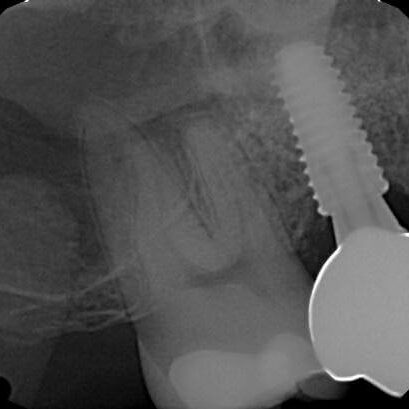

ULTRASONICS: Complications of Abutment Screw Retrieval Secondary to Prior Ultrasonic Attempts

There has been much written on the use of ultrasonics in retrieving fractured screw fragments, which I didn’t think a lot about until May of 2023, as it has not been a part of my fractured screw retrieval algorithm.